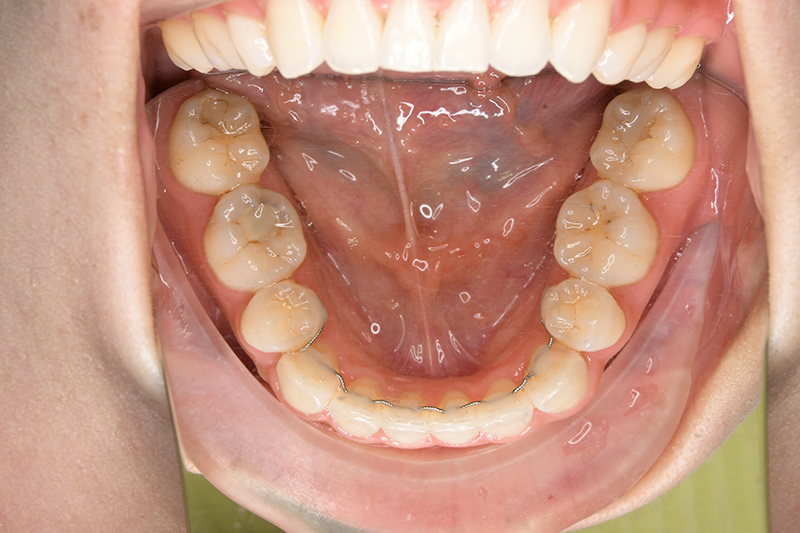

| 保定装置 | 上顎 Begg Type Retainer、下顎 Fix Type Retainer | ||||||

| 口腔内所見 | over jet 4.5mm、over bite 4.0mm、大臼歯関係 I級で上下顎前歯部に叢生が認められた。 |

| 批評・予后 | 叢生が大きかった影響もあり、治療期間は20ヶ月と比較的短い期間が終了できた。治療後においては口元の改善、咬合の緊密化は達成できたように思う。 |